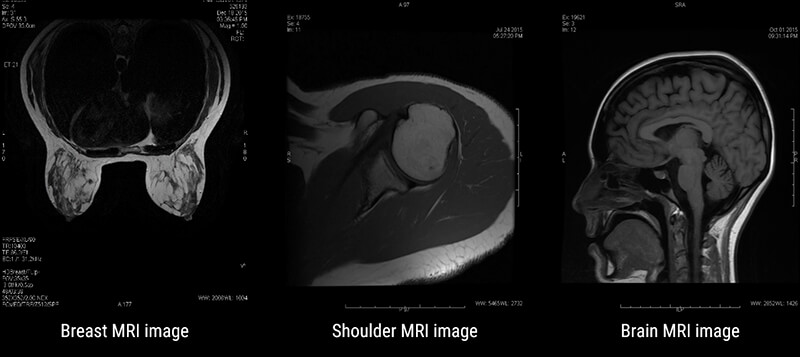

MRI has many applications in medical imaging. It is best known for its superb spatial resolution or the ability to resolve fine detail and small objects. Some of the most common applications are: Musculoskeletal or MSK, Neurological studies, functional studies, liver imaging, breast imaging and even cardiac imaging.

In MSK work, MRI is useful for looking at joints, tendons, muscles, bones, and vascular structures. Neurological imaging allows us to follow Multiple sclerosis progression and even allows for determining active lesions vs. chronic lesions. And breast imaging is a way to look closer at breasts without the use of ionizing radiation. These are just a few examples of the multitude of uses of MRI.

As with any imaging test or procedure, MRI is not without disadvantages, but the advantages of MRI far outweigh them. Advantages of MRI include superb detail, or spatial resolution. MRI also allows us to evaluate the tissue in question from various angles or what we refer to as Mulitplanar imaging, allows us to see tissue using various weighting, each giving different information about the tissue, and the ability, in some cases, to image joint spaces and the spinal cord without the use of contrast media. This is particularly important when the patients have contraindications to the contrast used in radiography.